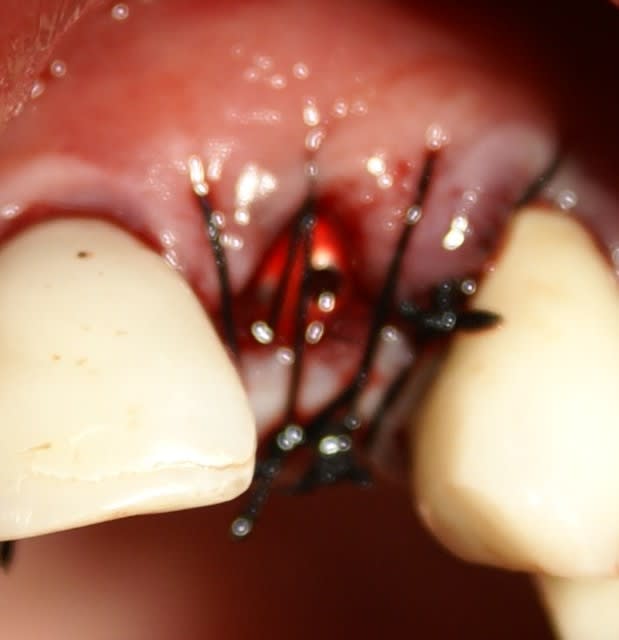

Tout à fait d'accord growler et c'est d'ailleurs ce que l'on peut voir sur le cas suivant. Fracture radiculaire, aucune infection periradicualire. Extraction et implantation immediate. Espace existant entre l'implant et l'alvéole est comblé par du BioOss. Un logement sous gingival est formé en vestibulaire et palatin de facon à pouvoir recouvrir le tout par BioGide et un conjonctif enfoui.

L'implant est de 15mm mais l'alvéole était large et 50% environ de la surface implantaire n'était en contact qu'avec du BioOss. J'ai pour cela préféré enfouir.

j'ai d'abord enfoui le plus apicalement possible ma membrane car je devais en premier lieu combler avec le moignon en place de manière à ne pas mettre de substitut osseux dans l'hexagone interne. Une fois mon substitut en place je travail le porte implant qui sert de support à la provisoire, il y a donc montages et démontages successifs.

Comme tu l'as si bien remarqué, j'ai laissé une minuscule languette de membrane, je l'a tracte très légèrement (une fois seulement la provisoire validée et prête à poser) et la fixe en la transperçant avec le moignon portant la provisoire. ainsi je recouvre bien le substitut osseux en palatin et en vestibulaire également.